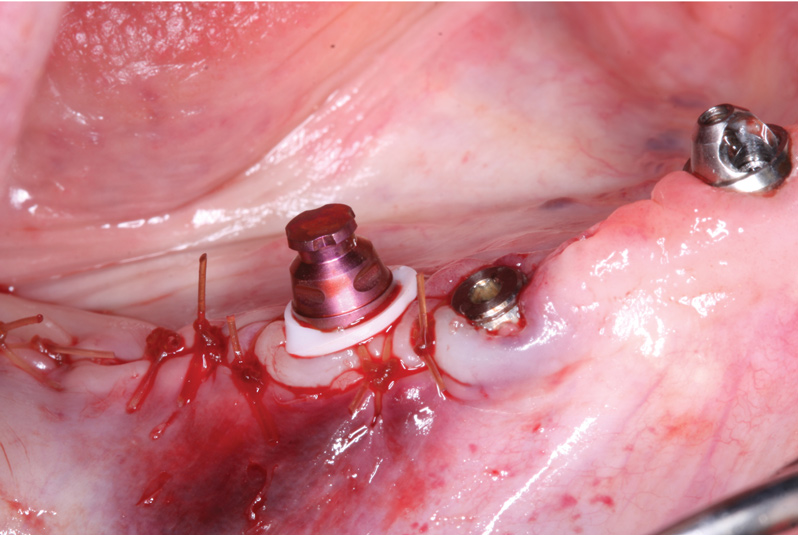

After achieving primary closure with a 4.0 chrome gut suture (Figure 16), a denture attachment housing and white spacer were placed onto the LOCATOR F-Tx abutment and pivoted into the correct orientation (Figure 17), creating an easily drawn path of insertion and removal for the PMMA prosthesis. To limit vertical and rotational movement, contribute to stability, and lock the prosthesis into place, the denture attachment housing features grooves and flats that ensure the housings remain locked into place within the prosthesis. Internally threaded to accept polyether ether ketone (PEEK) retention balls and a processing ball that snaps into the abutment, the attachment housing eliminates otherwise intensive chairside procedures to retain the screw-retained prosthesis.

Fig 16. Primary closure was achieved using a 4.0 chrome gut suture.

Figure 16

Fig 17. A denture attachment housing and white spacer were placed onto the LOCATOR F-Tx abutment and pivoted into the correct position and angulation.

Figure 17